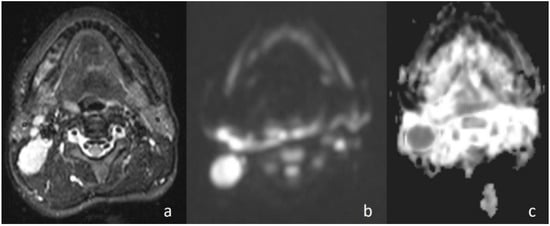

Figure 4. Second branchial cleft cyst. (a) Axial T2WI shows a unilocular cystic mass in the left carotid space; (b) the lesion shows low signal intensity on DWI; and (c) the lesion is hyperintense on the ADC map (ADC value of 2.02 × 10−3 mm2/s).

Apparently higher ADC values for benign cystic masses may be expected because of the relatively freer mobility of water protons in the fluid. In the current study, cystic masses were not grouped separately due to low numbers. However, consistent with previous studies, the mean ADC value of three cystic masses (Figure 4) (1.98 × 10−3 mm2/s) was higher than that of other benign solid masses (ADC = 1.48 × 10−3 mm2/s). In addition, the differences in ADC values among cystic masses could be explained by the different protein concentrations. A high protein level restricts the movement of water molecules by increasing the viscosity [15].